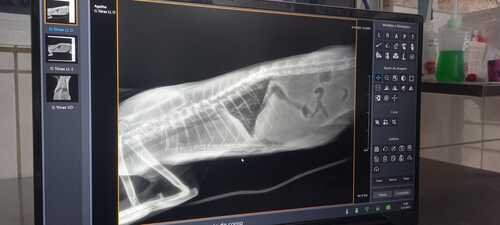

Fomos na oncologista que infelizmente confirmou que todos os problemas de saúde da nossa heroína são devidos a um linfoma que está empurrando o seu coração, apertando o seu peitinho.. Fizemos o teste e ela deu como FELV positivo, infelizmente. Isso deixa o caso ainda mais complicado.

Só que os custos vão ficando muito caros, internação, exames, tirar e examinar o líquido, raio x, exame de sangue, ultrassom e até um exame cardiológico pois suspeitamos que seja o coração.